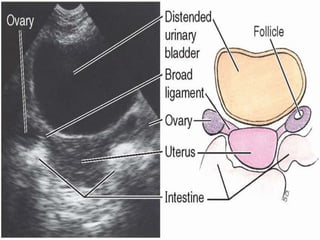

The urinary bladder develops during the 18th week of fetal development. It is located in the pelvic cavity behind the pubic symphysis in males and anterior to the uterus in females. The bladder has a muscular wall and receives its blood supply from branches of the internal iliac artery, including the superior and inferior vesical arteries. Nerve supply comes from pelvic splanchnic nerves via the hypogastric plexus and pudendal nerves. The bladder drains lymph into pelvic lymph nodes and is supported by ligaments attached to surrounding structures in the pelvis. Microscopically, it has a mucosa, submucosa, muscularis and adventitia layers.